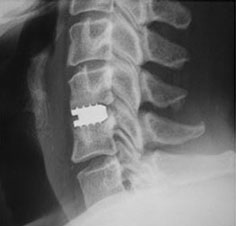

レントゲン 側面像

脊椎・脊髄疾患 : 頚椎前方除圧固定術(ケージを使用した手術)

頸椎症や、頚椎椎間板ヘルニアで神経を圧迫している部分が、神経より前方(のど側)にある場合に、のどのあたりから入って、あっぽあくの原因となっているものを取り除きます(除圧)。その後、除圧した上下の骨を固定します。その際チタン製のケージという医療材料を使用して、骨と骨が療合するまでの間の固定の補助とします。

椎間板が取り除かれたままでは、上下の骨がゆるい状態になるため、チタン製のケージを挿入し、上下の骨をしっかり固定します。

頚椎前方除圧固定術で使用するチタン製ケージ